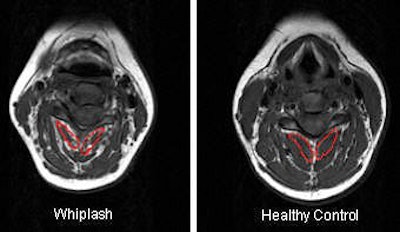

| Segmental muscles on T1-weighted MRI axial scan at C6 segmental level in a healthy control. All images courtesy of James Elliott. |

For the image analysis, regions of interest (ROI) were drawn over each bilateral cervical extensor muscle on the axial T1-weighted images at each vertebral segment (C0-C7). The authors also tested the reliability of MRI in this setting.

We used conventional MRI to quantify these muscular changes (because) we wanted to do a study that was clinically friendly. We wanted (our MRI protocol) to replicate one used in a standard practice, and thus ran a conventional T1-weighted scan of the cervical spine lasting 11 minutes. We also ran standard T2-weighted sagittal scans, but only to set up our axial scans.